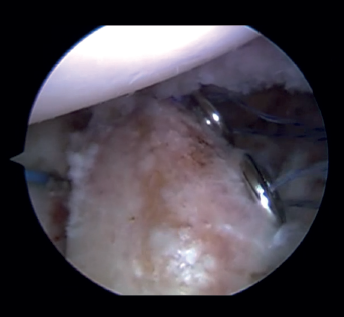

Capsulolabral repair (Figure 5)

After confirming the correct position and stability of the graft, capsulolabral tissues are repaired using glenoid implants, leaving the graft extra-articular.

Figure 5. View from the posterior portal (left shoulder). Capsulolabral repair by means of glenoid implants, leaving the graft in an extra-articular position.